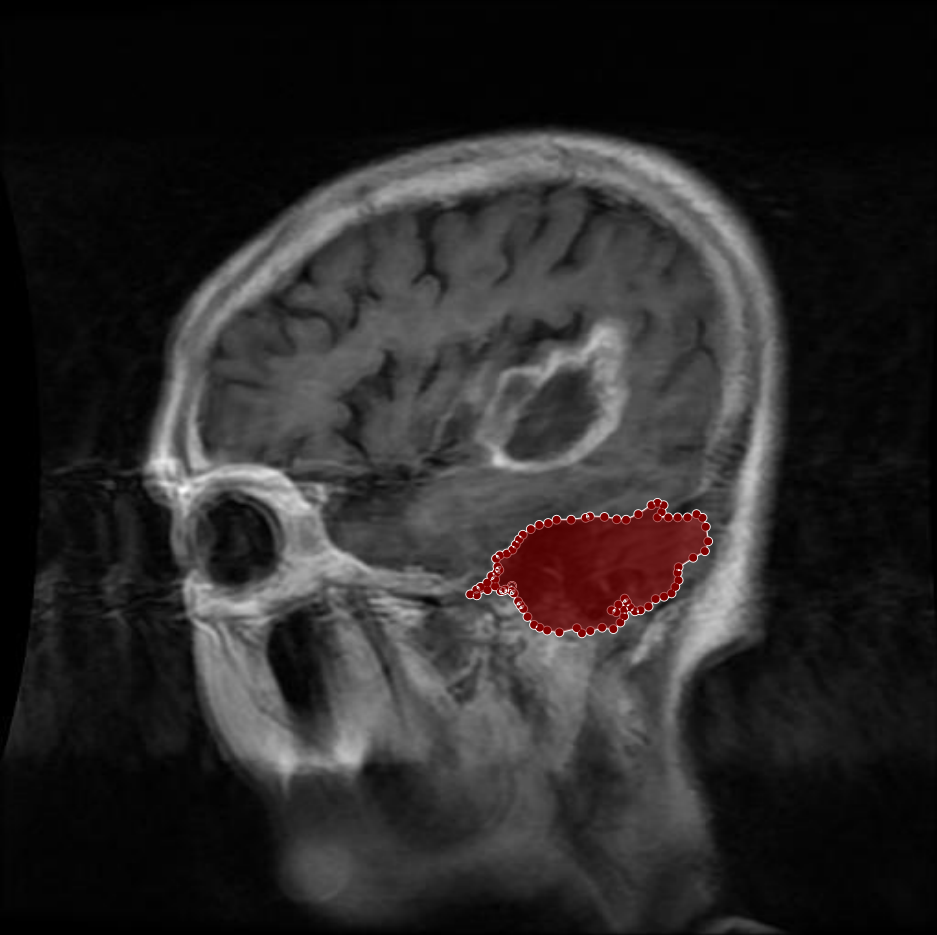

Figure 6: Samples of partial-region overannotations. The red area indicates regions that were initially marked as tumorous but were later identified by the radiologist and physician as non-tumorous.

In other instances, certain areas that were mistakenly included as part of the tumor region were refined based on radiologist and physician feedback. These areas, though visually similar to tumor tissue, were determined to be non-tumorous upon closer examination. As illustrated in Figure 6, the removal of these incorrect segments resulted in more precise tumor masks and enhanced the reliability of the dataset.